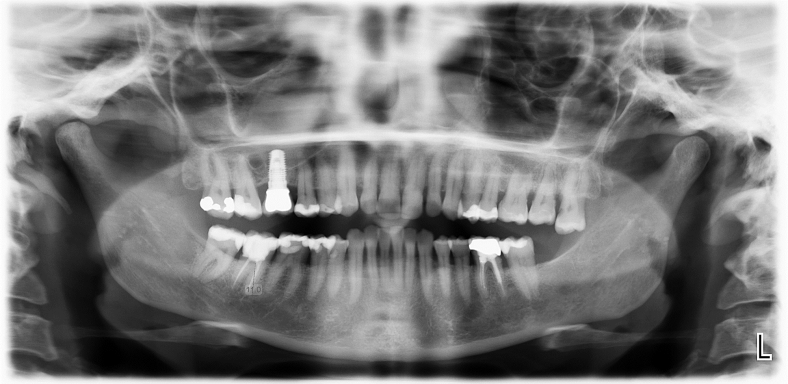

Die Implantat Entfernung in unserer Praxis

Bei der Implantat- Entfernung wird sehr genau gearbeitet, sodass keine Titanpartikel durch die Ausbohrung im Knochen zurückbleiben. Die Entfernung von Titanimplantaten erfordert nicht nur eine fachmännische chirurgische Technik, sondern auch eine umfassende Nachsorge (z.B. Schwermetallausleitung), um eine schnelle Genesung zu gewährleisten.

Unsere Praxis ist mit neuen Technologien und Materialien ausgestattet, um diesen Prozess so schonend wie möglich zu gestalten. In der Regel ist es möglich, die Titanimplantate aus dem Knochen herauszudrehen, ohne einen Knochendefekt zu hinterlassen.

Nach der Entfernung der Titanimplantate können bei gesundem Knochen Keramikimplantate sofort gesetzt werden. Mit dem unmittelbaren Austausch von Titan zu Keramik wird Zeit gewonnen, so kann das neue Implantat in dieselbe Stelle eingearbeitet und Knochenverlust vermieden werden.